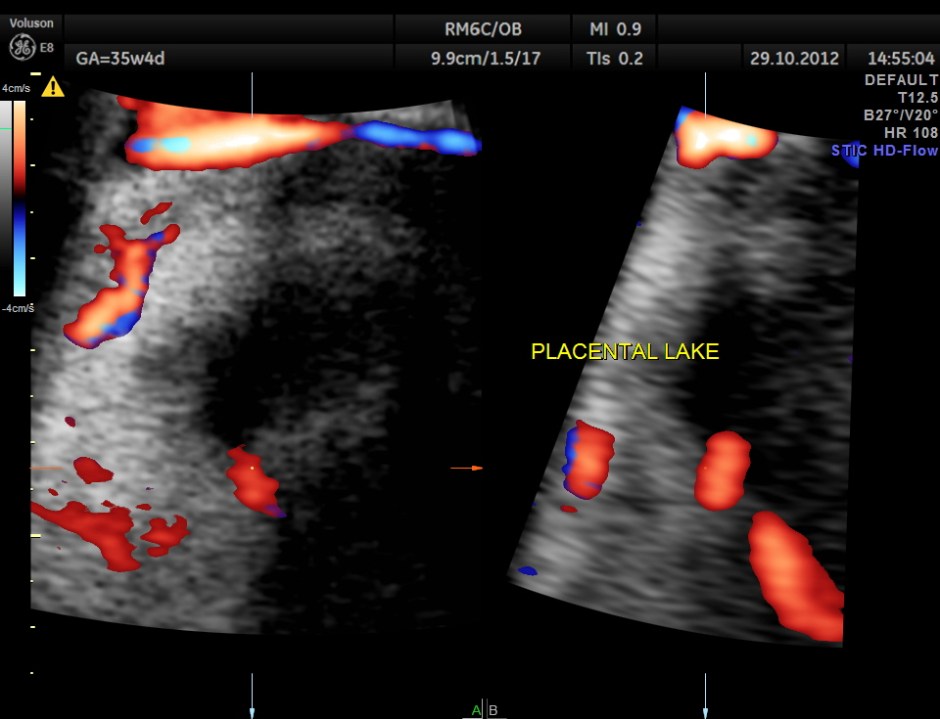

apart from this the placenta showed a few lakes and a localised mass , probably chorio angioma